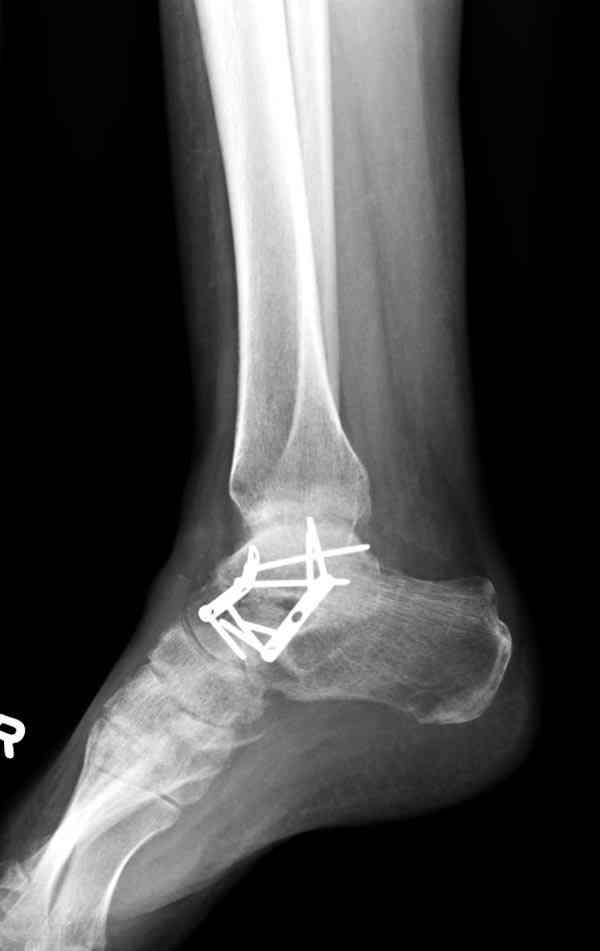

Случай с множественным оскольчатым переломом тарана оперированный из двойного доступа.

Через 8 мес.:

Через 14 мес.: